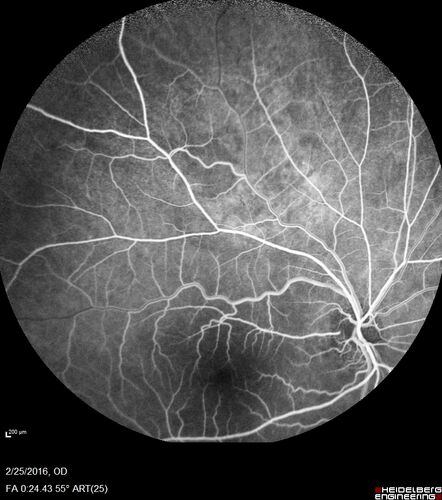

Amelanotic Choroidal Nevus - Multimodal Imaging

61 year old man with amelanotic choroidal nevus. Vision Normal - Stable over 4 years.